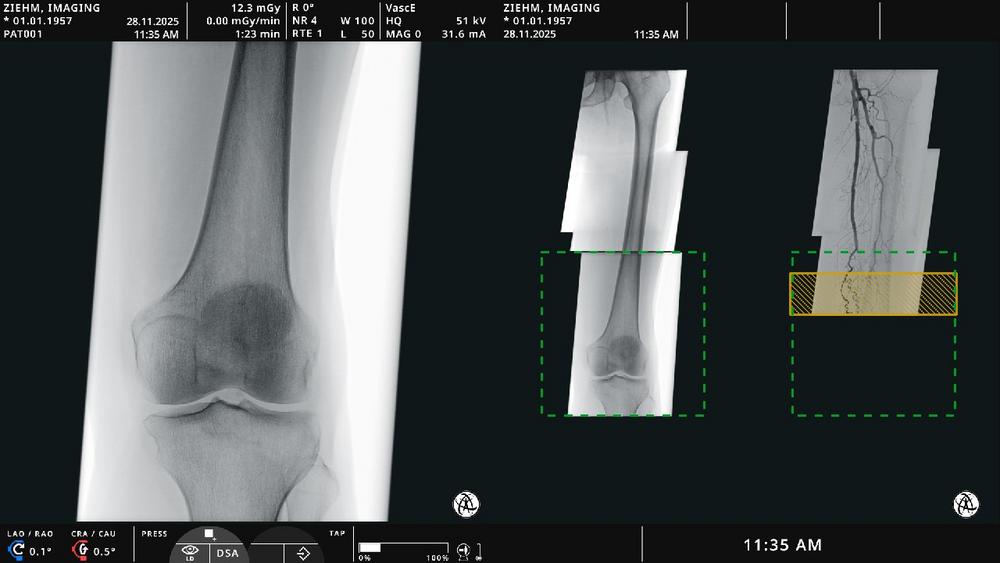

Auf dem diesjährigen European Congress of Radiology (ECR 2025) präsentiert Ziehm Imaging erstmalig seine Innovation für Gefäßchirurgie. Das neue Softwarepaket, das als Teil der mobilen Hybridraumlösung verfügbar ist, unterstützt bei endovaskulären Eingriffen mit Planung, Navigation und Fusionsbildgebung. Die Markteinführung wird direkt auf der ECR stattfinden. Erste klinische Nachweise wurden bereits […]